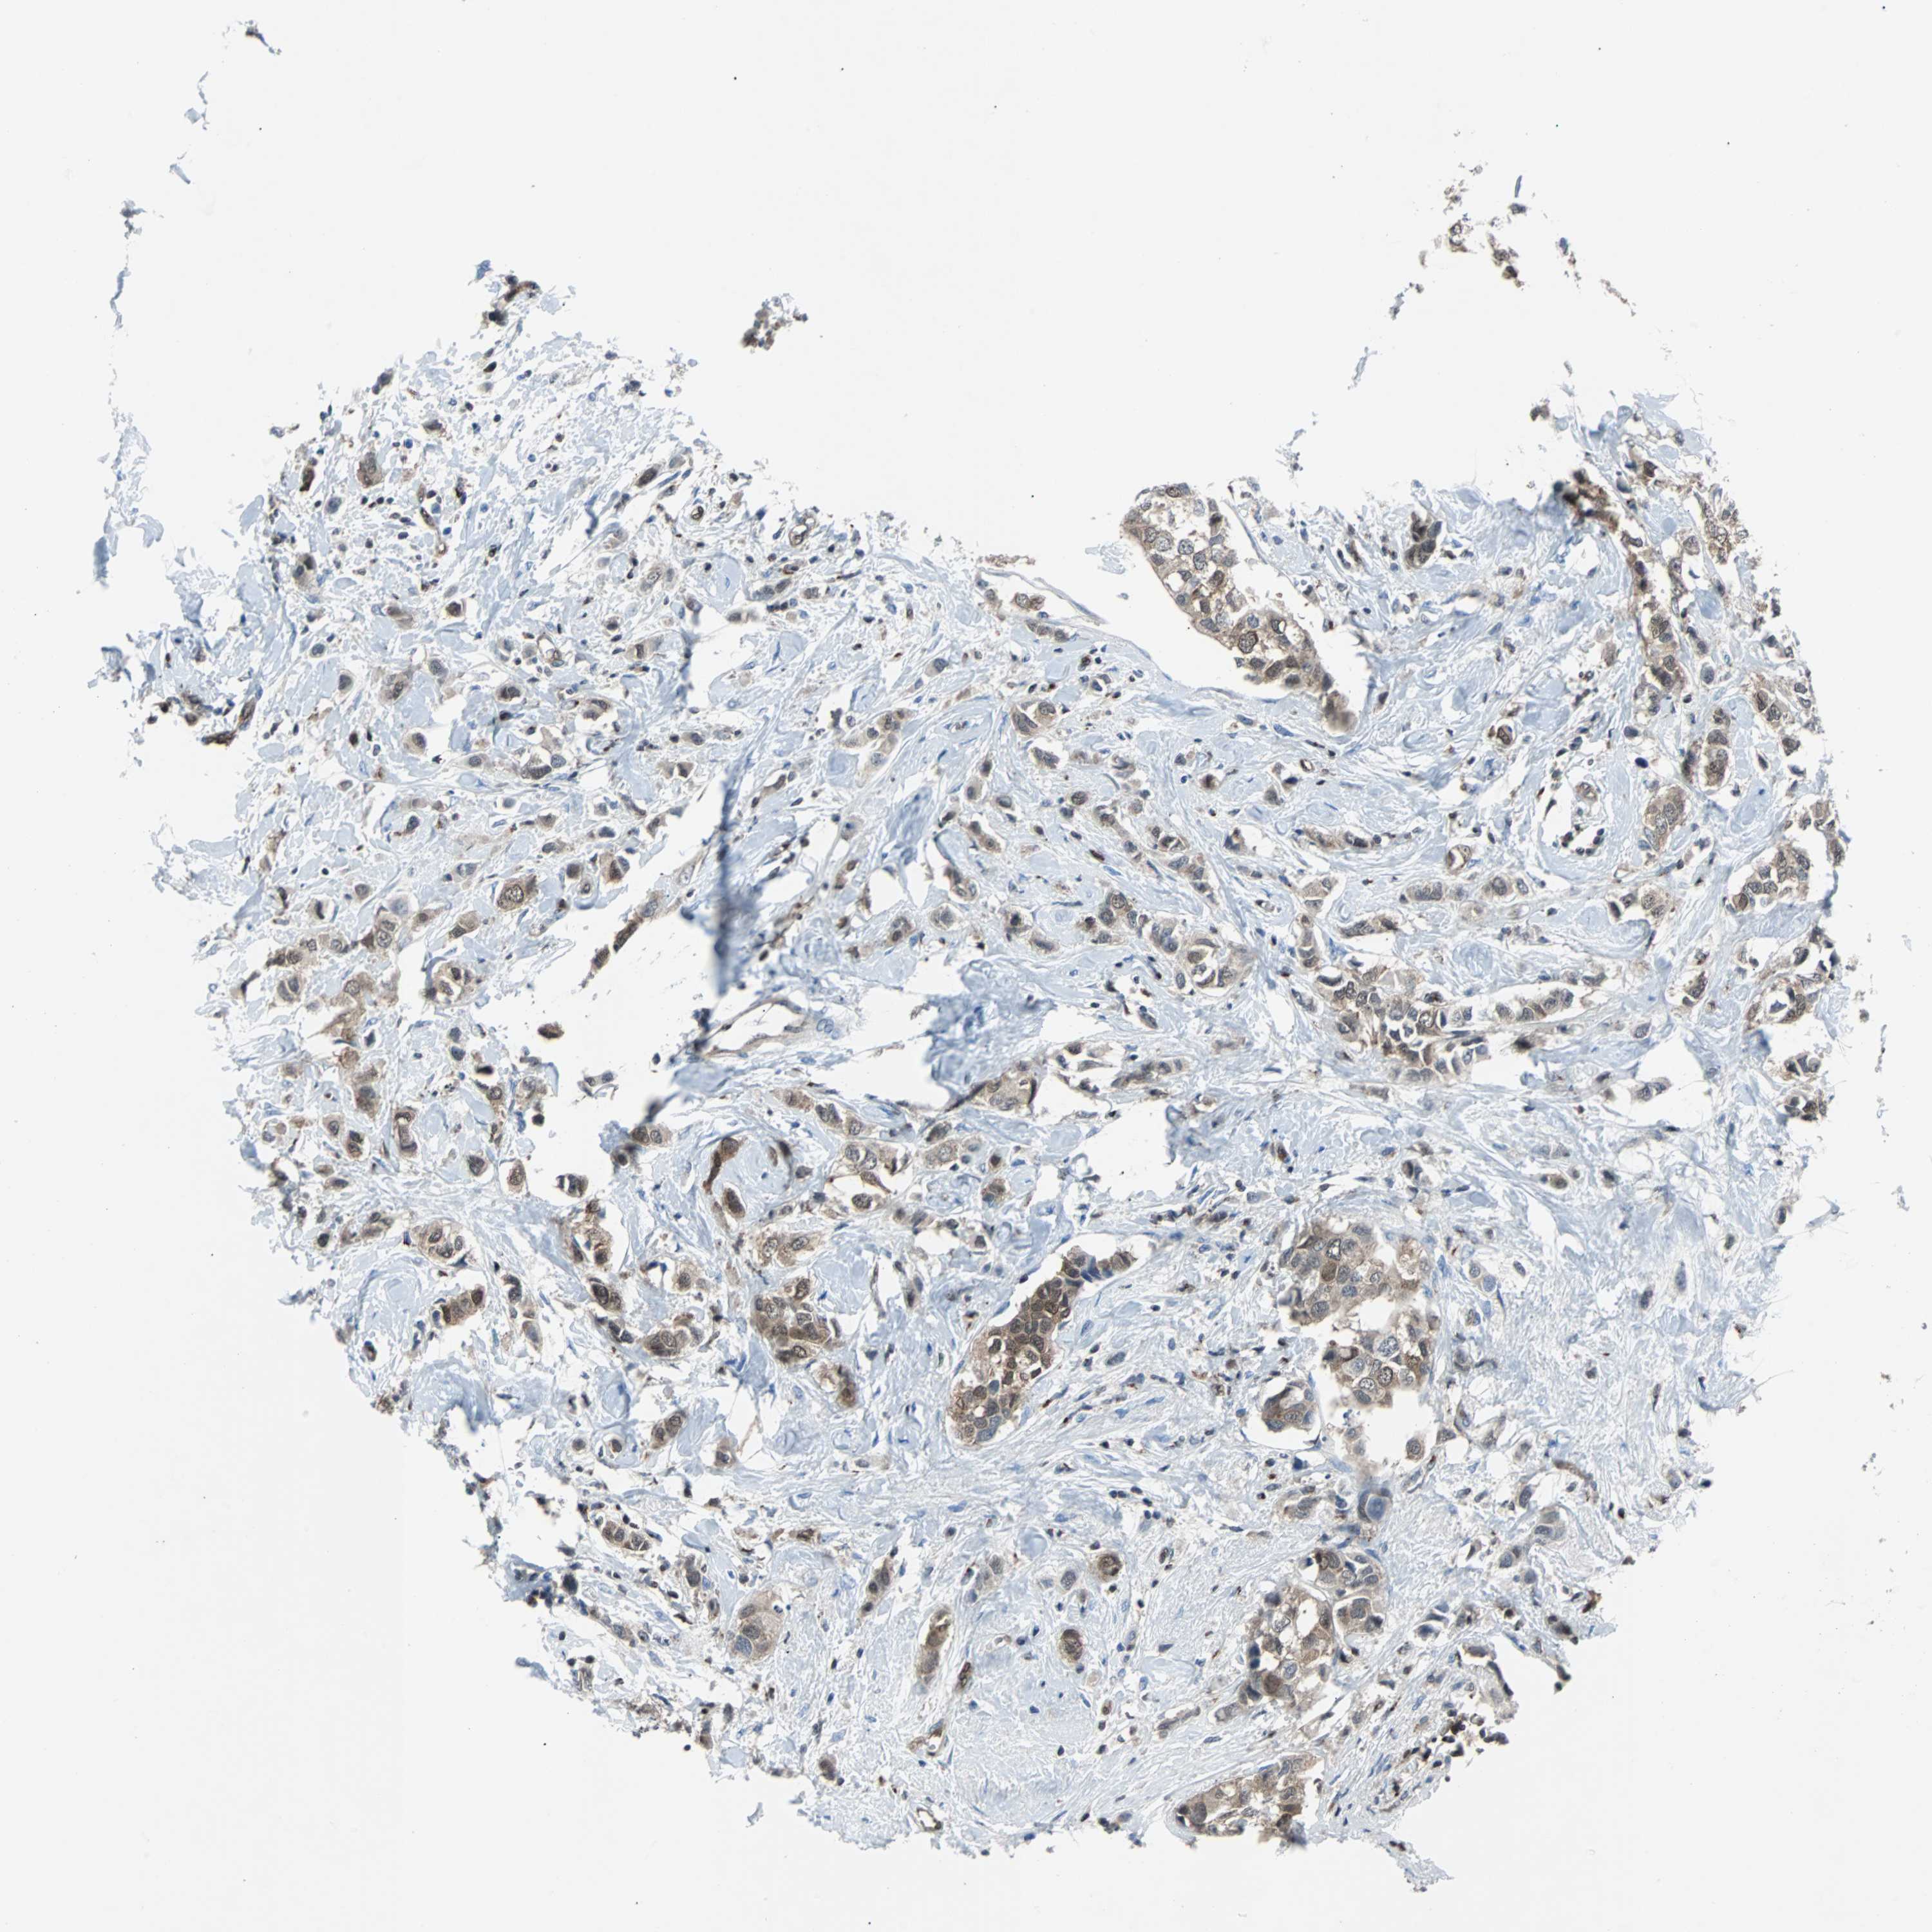

CANCER BREAST CANCER Show tissue menu

BRCA TCGA BRCA VALIDATION PROTEIN EXPRESSION

Breast cancer

Human cancer

MAP2K6 is potential prognostic, high expression is favorable in Breast Invasive Carcinoma (TCGA)